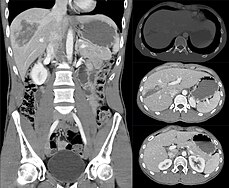

From Handwiki | Liver injury | |

| A watercolour painting of a liver with extensive rupturing caused by blunt trauma to the abdomen. |

A liver injury, also known as liver laceration, is some form of trauma sustained to the liver. This can occur through either a blunt force such as a car accident, or a penetrating foreign object such as a knife.[1] Liver injuries constitute 5% of all traumas, making it the most common abdominal injury.[2] Generally nonoperative management and observation is all that is required for a full recovery.